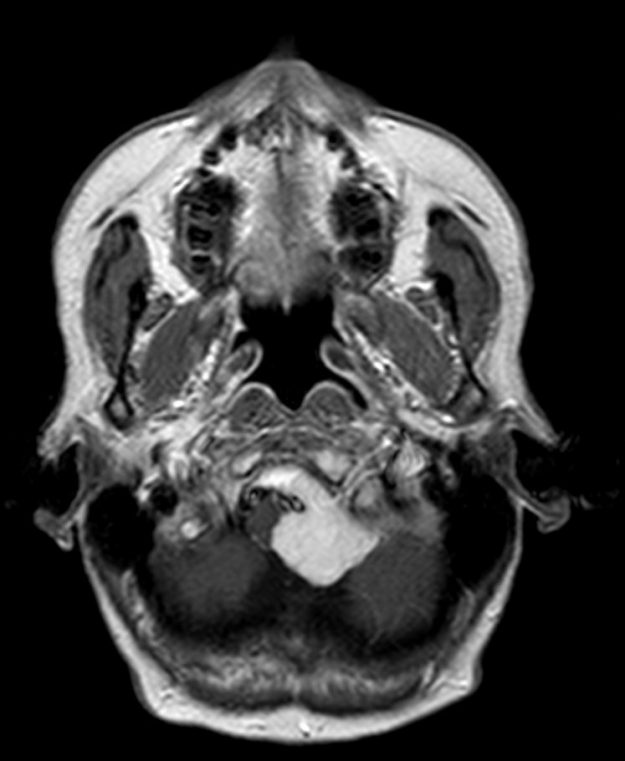

Μηνιγγίωμα περιοχής Επίφυσης

Ασθενής γυναίκα, 52 ετών η οποία παρουσίασε υπακουσία και επεισόδια πάρεσης του προσώπου. Ο απεικονιστικός έλεγχος με μαγνητική τομογραφία ανέδειξε ευμεγέθη όγκο στην περιοχή της επίφυσης (κωνάριο) με πίεση επί του μεσολοβίου, του τετραδύμου πετάλου και λοιπών εν’ τω βάθει δομών. Διενεργήθη δεξιά ινιακή, διασκηνιδιακή, διαδρεπανική προσπέλαση και ολική αφαίρεση της βλάβης. Η μετεγχειρητική αξονική…